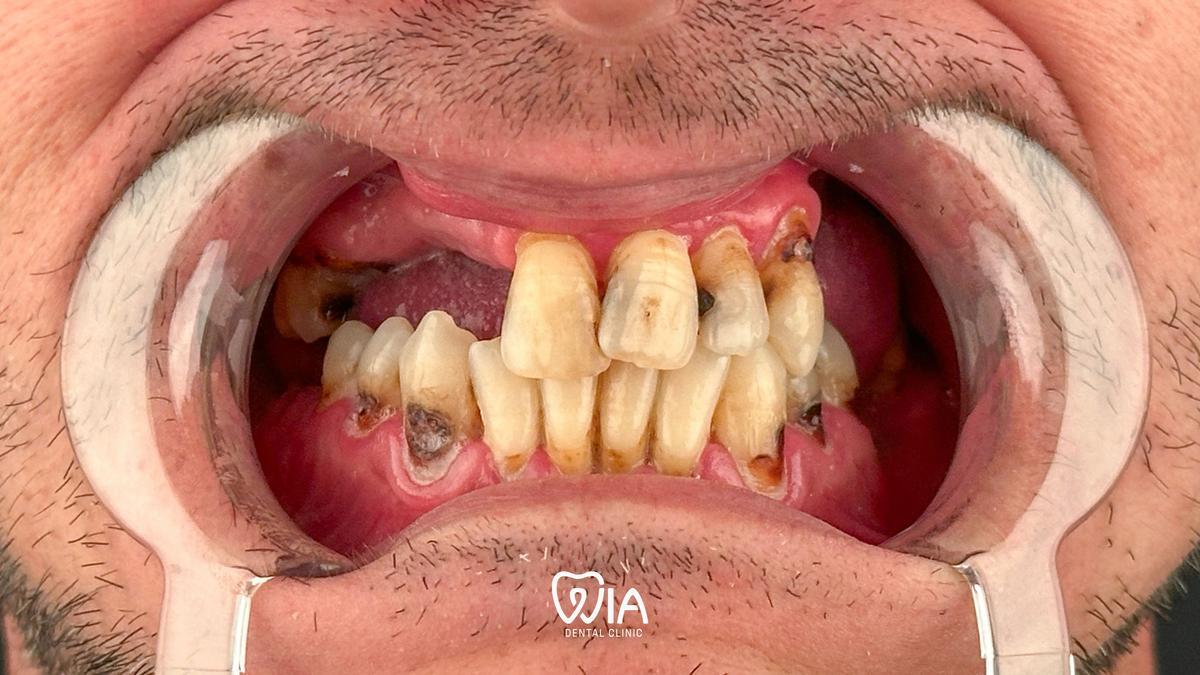

Real stories from real people

Real results of our patients